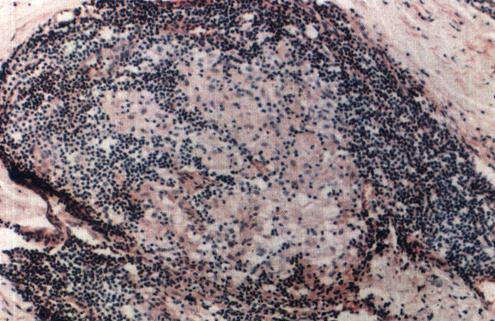

2.BT(界线类偏结核样型)此型麻风比TT或BB更为常见,大多数病人不治疗将降级,随着治疗可升级。

为上皮样细胞肉芽肿,伴有巨细胞或者中等量的淋巴细胞,或者两者兼备,巨细胞为异物型。表皮偶有小范围的楔状浸润或侵蚀,有时可见狭窄的表皮下带,神经束中等度肿大,神经内可有肉芽肿病变且常常有淋巴细胞浸润,神经束膜轻度层状改变,有时仅见雪旺氏细胞增生,抗酸杆菌0~2.5+(照片3)。

照片3 界线类偏结核样型麻风(BT)

表皮下有“无浸润带”,浸润灶以上皮样细胞为主,周围淋巴细胞较少。